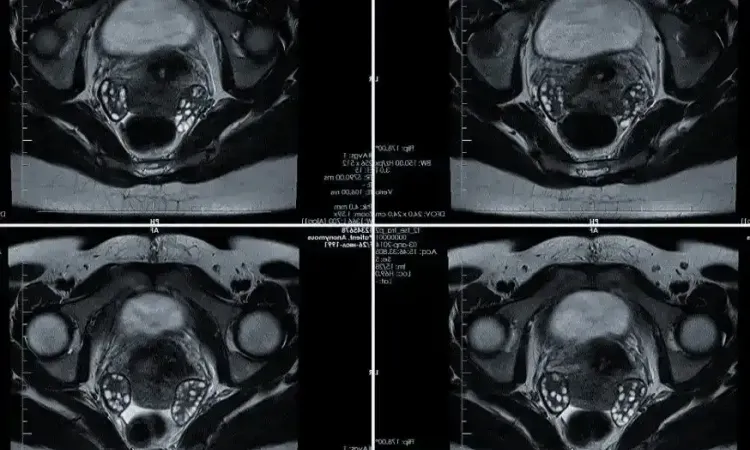

МРТ органов малого таза

МРТ органов малого таза – это высокоточный метод диагностики, применяемый для изучения репродуктивных органов мужчин и женщин, мочевого пузыря, прямой кишки и других прилегающих структур. В основе методики лежит принцип магнитного резонанса. Обработка полученных данных проводится при помощи специальной компьютерной программы.